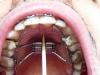

Киборг Опубликовано 10 октября, 2009 Поделиться Опубликовано 10 октября, 2009 (изменено) Надеюсь не обидится на меня Lea, я решил не создавать новой похожей темы, отпишусь здесь. 26 лет, год уже ношу брекеты, но не в этом суть, вобщем позавчера поставили мне расширитель на в.ч. Хотел узанть на сколько он должен прилегать к небу? Аппарат делали по слепку, но у меня в спокойном положении,при том что рот закрыт, расширитель лежит на языке, постоянно выделяются слюни, не могу нормально говорить, и от железки и от того что рот в слюнях. От расширителя до неба, ближе к передним зубам около 5 мм, сзади, другая сторона, до неба - 7мм. Не могу ни нормально глотать, ни сплюнуть, ни есть - все туда забивается. Если это все приплюсовать к брекетам с которыми я мучаюсь уже год, это вообще кошмар.Как быть с гигиеной с внутренней стороны в.ч. , если там эта железка?Выкладываю фото. Изменено 10 октября, 2009 пользователем Киборг Ссылка на комментарий

Orthodoc Опубликовано 12 октября, 2009 Поделиться Опубликовано 12 октября, 2009 Надеюсь не обидится на меня Lea, я решил не создавать новой похожей темы, отпишусь здесь. 26 лет, год уже ношу брекеты, но не в этом суть, вобщем позавчера поставили мне расширитель на в.ч. Хотел узанть на сколько он должен прилегать к небу? Аппарат делали по слепку, но у меня в спокойном положении,при том что рот закрыт, расширитель лежит на языке, постоянно выделяются слюни, не могу нормально говорить, и от железки и от того что рот в слюнях. От расширителя до неба, ближе к передним зубам около 5 мм, сзади, другая сторона, до неба - 7мм. Не могу ни нормально глотать, ни сплюнуть, ни есть - все туда забивается. Если это все приплюсовать к брекетам с которыми я мучаюсь уже год, это вообще кошмар.Как быть с гигиеной с внутренней стороны в.ч. , если там эта железка?Выкладываю фото. По снимку оценить качество постановки аппарата сложно, все неприятные ощущения, изложенные выше, должны уменьшиться к концу первой недели ношения. После приема пищи полощите рот, винт чистите зубной щеткой два раза в день. Ссылка на комментарий

Киборг Опубликовано 12 октября, 2009 Поделиться Опубликовано 12 октября, 2009 По снимку оценить качество постановки аппарата сложно, все неприятные ощущения, изложенные выше, должны уменьшиться к концу первой недели ношения. После приема пищи полощите рот, винт чистите зубной щеткой два раза в день. Ну по миллиметрам примерно можно сказать? На сколько он должен прилегать к небу? У меня там 5-7 мм получается, не ужели столько необходимо? Ссылка на комментарий

Orthodoc Опубликовано 15 октября, 2009 Поделиться Опубликовано 15 октября, 2009 Мда...Это зависит от формы неба, иногда винт при изготовлении аппарата не уложить на правильную глубину (в идеале, он должен отстоять на 3-4-мм от слизистой неба.) Ссылка на комментарий